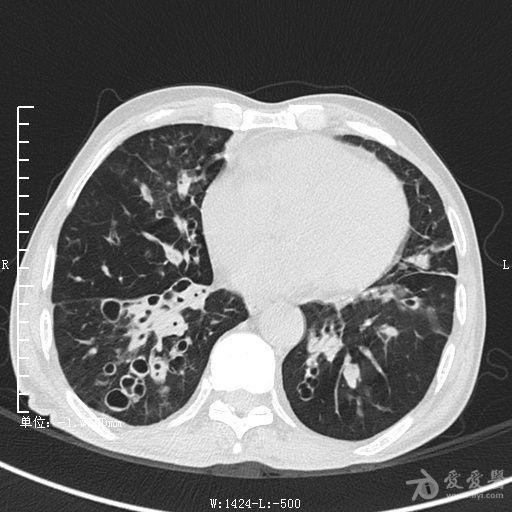

典型支气管扩张及肺水肿CT片

典型支气管扩张肺水肿